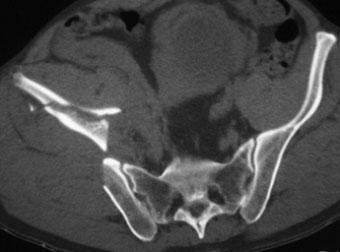

高能量的(猛烈撞击)骨盆骨折常伴有危及生命的大出血,失血性休克发生的比率比四肢和脊柱骨折高出40%。盆腔骨折主要的死亡原因包括出血,多脏器衰竭和脓毒血症,这是骨盆骨折需要除外盆腔腹膜后出血和进行包括动脉栓塞等干预治疗的原因。

盆腔创伤出血的主要来自(1)静脉/静脉丛的破裂、(2)网状骨质(cancellous bone)的弥漫性出血和(3)动脉出血或(4)三种出血的联合。出血往往是最常见的可治疗的死亡原因。严重盆腔出血往往由于不稳定和严重盆腔骨折。骨出血和静脉出血占80-90%,可以通过骨盆固定得到治疗。动脉出血占10-20%,主要治疗方法为栓塞。Hemodynamically unstable pelvic fractures. Injury. 2009

盆腔创伤的血流动力学可以是稳定和不稳定两种。低血压和盆腔骨折有关吗?需要通过MDCT观察出血源。

问题是骨折后出血的来源经常是不清楚的,有时候有可能出血来自盆腔以外的实质脏器出血或腹部实质脏器和盆腔骨折都参与供血。如果容量补充后仍然不稳定需要尽快确定是否动脉来源出血。检查方法的选择根据临床情况不同选择不同。特别是复合伤患者如从高空坠落,很难判读